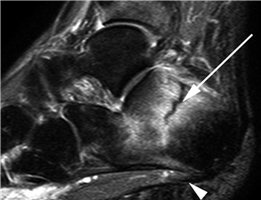

Clinical & Radiographic Imaging Archive

Clinical Image